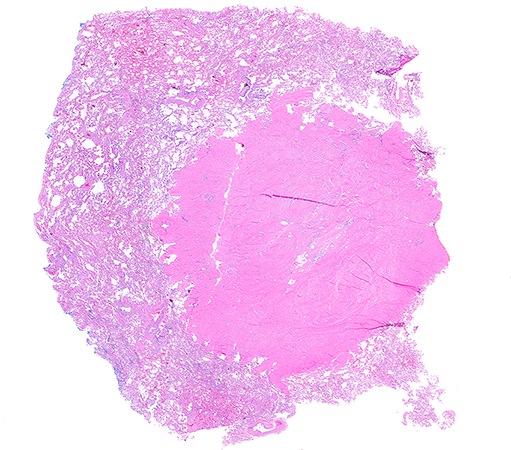

Clinical History: A 70-year-old man with past medical history of prostate cancer status post prostatectomy and long-standing history of smoking was found to have a 1.5 cm right upper lobe nodule on a surveillance chest CT scan. A bronchoscopic biopsy yielded non-diagnostic findings and a right upper lobe wedge resection was performed. Grossly, the lung wedge contained a 1.5 x 1.2 x 1.1 cm tan-white, dense fibrous lesion with ill-defined borders. Frozen section evaluation showed dense fibrosis/scar and no malignancy. Permanent tissue sections confirmed a nodule composed of dense fibro-collagenous tissue with jagged borders (Figure 1). No leaf-like growth pattern was observed at the periphery of the lesion (Figure 2). In addition, the nodule contained focal mature adipose tissue, entrapped benign small airways and clefts of alveoli with reactive pneumocytes and few entrapped blood vessels (Figures 2, 3 and 4). Inflammation, calcifications, necrosis, atypia, and/or malignancy were not identified. Masson’s trichrome highlighted the collagenous stroma in blue and short fascicles of benign smooth muscle in red (Figure 5). By immunohistochemistry, the nodule was negative for STAT6 (not shown), with entrapped pneumocytes positive for TTF1 (Figure 6).

Pulmonary hamartomas occur commonly in adults and have a male predominance. They usually present as a single peripheral lung nodule without a specific lobe predilection. The WHO classification defines pulmonary hamartomas as “benign mesenchymal neoplasms with variable amounts of at least two mesenchymal elements and entrapped respiratory epithelium”. Histologically, hyaline cartilage is the most predominant element, followed by mature adipose tissue, myxoid stroma with bland spindle cells, smooth muscle, fibrous tissue and/or bone. The diagnosis is typically straightforward but may be problematic in cases where one of the less frequent elements predominates, particularly in a needle biopsy. Pulmonary hamartomas with abundant adipose tissue are called lipomatous hamartomas and those with abundant smooth muscle are designated adenomyomatous hamartomas. Those with a prominent fibrous component are rare. In all cases, the entrapped respiratory epithelium has bland cytology and there is no proliferation (Figures 1-4). At the molecular level, these neoplasms harbor the t(3;12)(q27-q28;q14-15) resulting in a HMGA2::LPP gene fusion implicated in chondrogenesis and adipogenesis. The optimal treatment of pulmonary hamartomas is surgical resection with excellent prognosis.